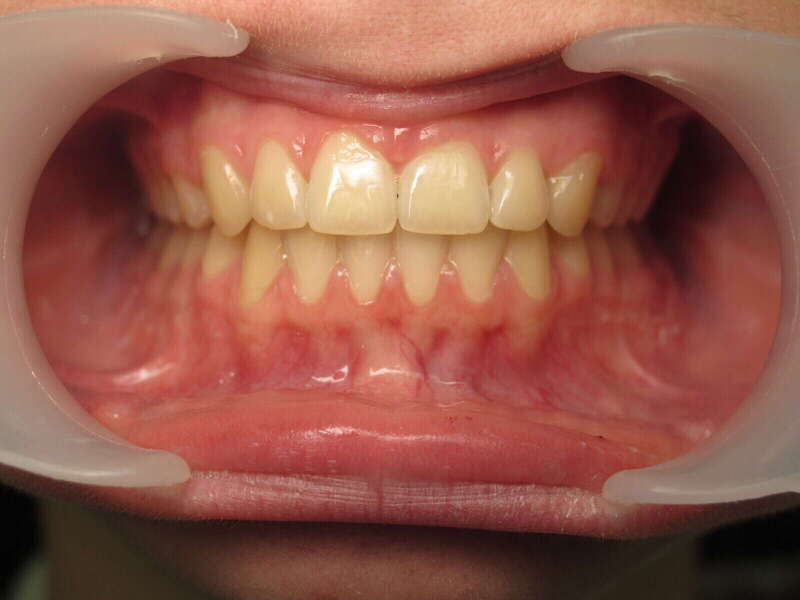

Cas n°1 traité par aligneurs - adolescent

Ce cas d’une adolescente illustre la correction d'une Classe II avec supraclusion par aligneurs. La stratégie thérapeutique a reposé sur une distalisation séquentielle de l'arcade supérieure. Ce mouvement précis a permis de reculer les dents maxillaires étape par étape pour annuler le surplomb (overjet) sans extractions.

Résultats clés :

• Correction fonctionnelle : Retour à un engrènement de Classe I stable et correction du recouvrement vertical.

• Esthétique restaurée : Harmonisation globale du sourire et du profil.

• Approche moderne : Un traitement discret, confortable et hautement prévisible.

Le résultat final montre une occlusion saine et un sourire parfaitement aligné, garantissant une santé dentaire et articulaire optimale pour l'avenir.

Avant

Après